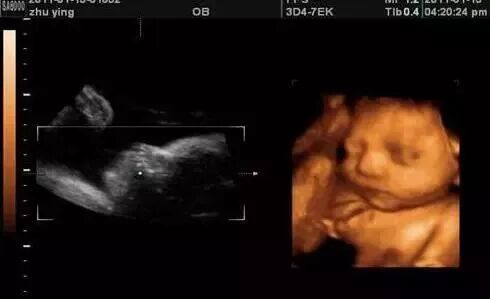

父母都希望自己的宝宝健健康康,所以,孕期定时产检,是最重要的事情了。整个孕期,宝妈们至少要进行3次或者3次以上的超声检查,其中孕中期的「四维彩超」最特别,这个检查是宝宝跟宝妈第一次「亲密接触」。透过先进的仪器,宝妈能直观的看到胎宝宝的模样和一举一动。

四维彩色超声诊断仪是目前世界上最先进的彩色超声设备。它能够多方位,多角度地观察宫胎儿的生长发育情况,为早期诊断胎儿先天性体表畸形和先天性心脏疾病提供准确的科学依据。

记录宝宝在妈妈肚子里的成长过程:四维彩超不仅可以让准妈妈感觉到宝宝的运动,而且可以亲眼目睹他们的一举一动和乖巧面容。另外还可以将宝宝的样子和动作制作成照片或录像,让宝宝拥有最完整的0岁相册,是很值得珍藏的。